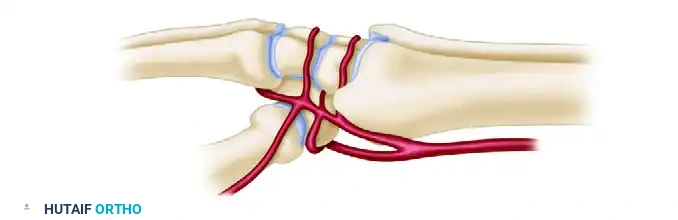

Lateral Arterial Perspective

The lateral circulation highlights the critical radial artery branches supplying the scaphoid tubercle and trapezium.

Clinical Pearl: The scaphoid and lunate rely heavily on retrograde intraosseous blood flow. The scaphoid receives 70-80% of its blood supply via dorsal ridge vessels entering distally, making proximal pole fractures highly susceptible to avascular necrosis (AVN) and nonunion.